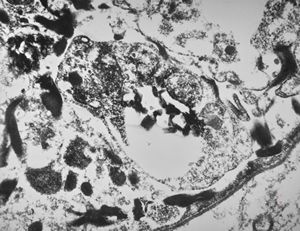

M, | cerebral cortex - malaric pigment